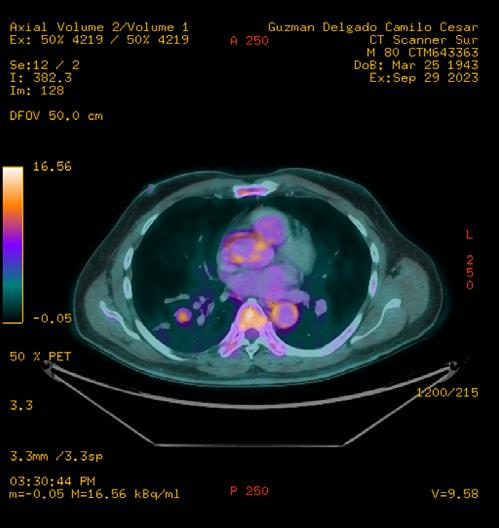

Posteriormente, se realiza estudio de PET-CT con 18FDG , con hallazgos de metabolismo asociado y SULmax de 2.0, se recomienda realizar biopsia.

Figura 5. Estudio de PET-CT con FDG que muestra hipercaptación del radiofármaco en el nódulo pulmonar, lo que traduce en metabolismo aumentado.